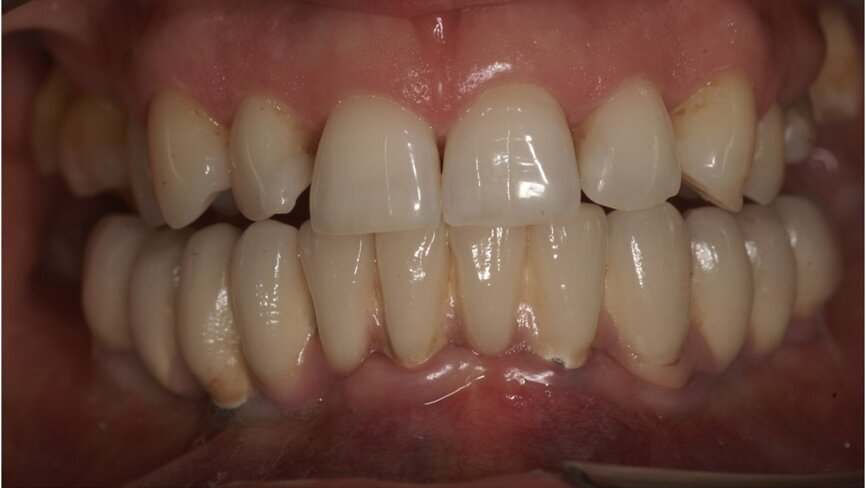

przygotowanej wcześniej protezie czasowej metodą bezpośrednią. Czasowe uzupełnienie protetyczne osadzono, używając cementu tymczasowego (Ryc. 5 i 6). Zlecono wykonanie zdjęcia techniką CBCT (Ryc. 7). Wizytę kontrolną wyznaczono następnego dnia, a szwy zostały usunięte po 10 dniach.

Po upływie 3 miesięcy czasowe uzupełnienie protetyczne (Ryc. 8) zostało wymienione na cementowaną pracę ostateczną (Ryc. 9),